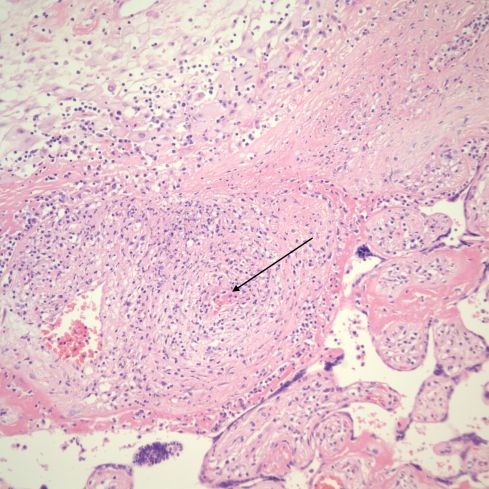

These lesions of larger stem villi may show endovascular lymphocytes and thrombus (Fig 24-26).

Fig 24) The stem villus shows eccentric inflammation and destruction of a portion of the vessel wall, and fibrin deposition. In the upper left corner the connecting and adjacent villi show VUE and the syncytial surface of the stem villus shows necrosis and lymphocytic inflammation. (H&E, 10x)

Fig 25)This stem vessel in an area of villitis shows lumenal thrombus and inflammation of the vessel wall. (H&E, 20x)